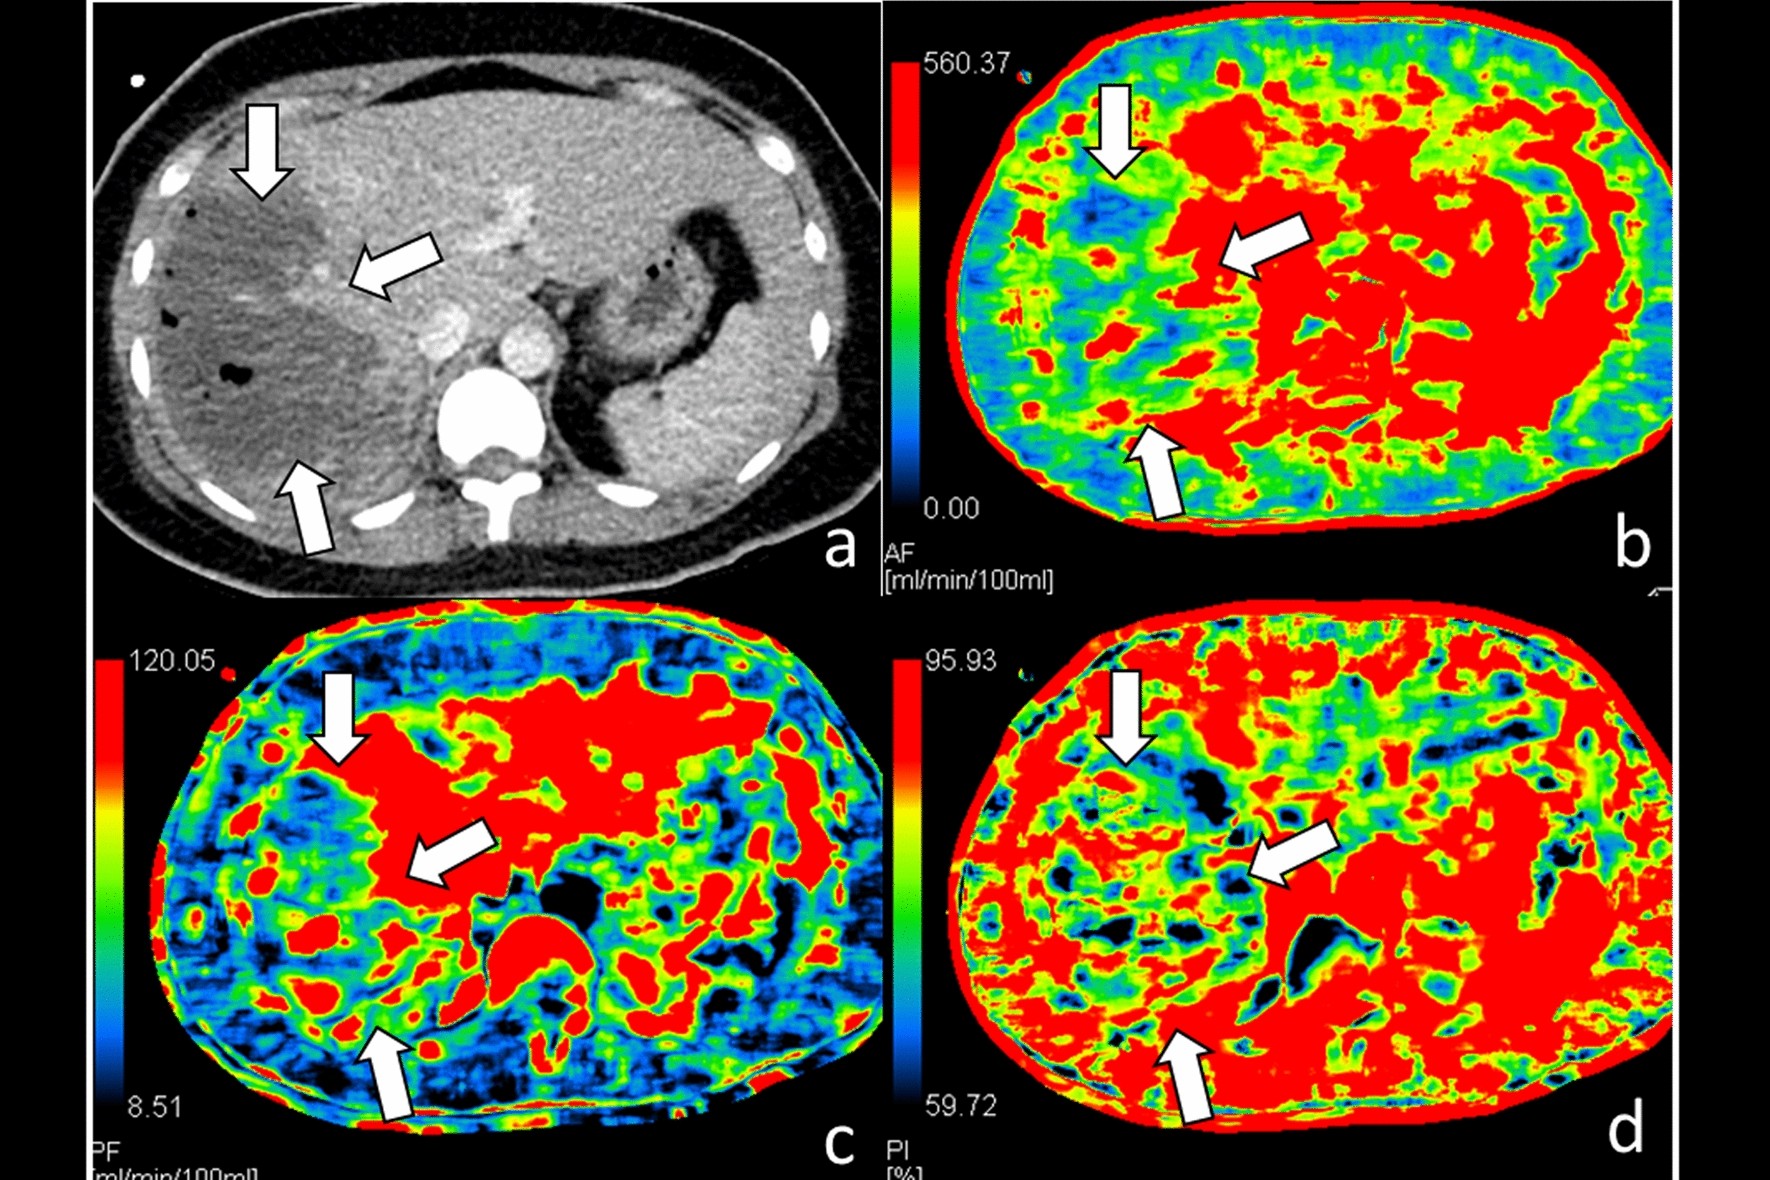

Figure 2

CT of a 34-year-old woman with grade IV liver injury at right lobe after embolization management. (a) Contrast-enhanced CT of the liver shows extensive right lobe injury (arrows); (b) hepatic arterial perfusion CT and (c) hepatic portal venous perfusion CT show decreased arterial and portal venous flows to traumatic parenchyma at right lobe (arrows); (d) hepatic perfusion index which is a ratio of arterial perfusion to the total hepatic perfusion is normal at traumatic parenchyma (arrows).